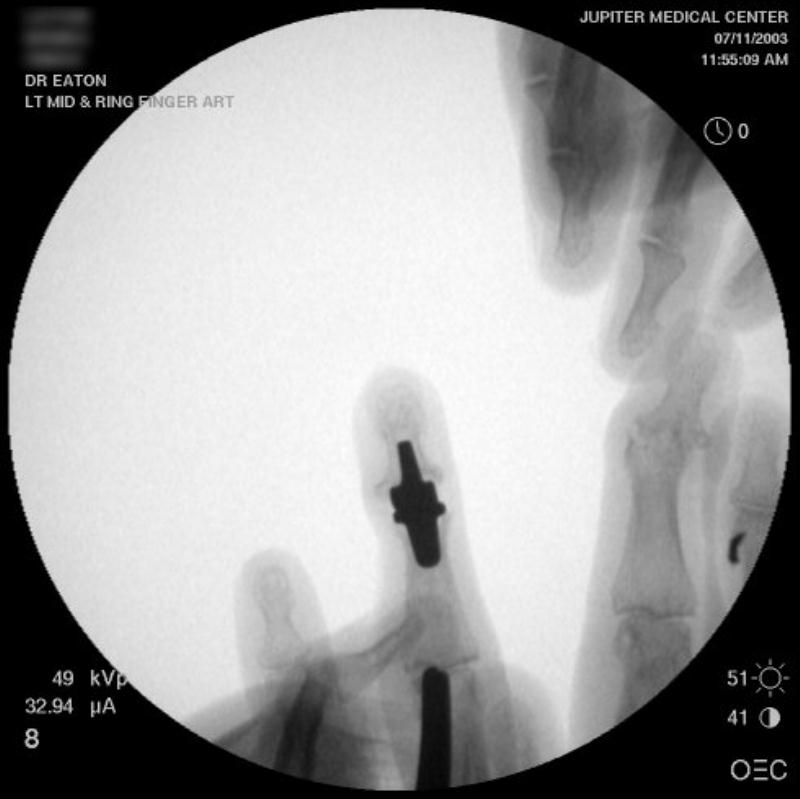

Intraoperative fluoroscopy using the same technique as above. The trial spacers:

The final implant:

Xrays one year out.